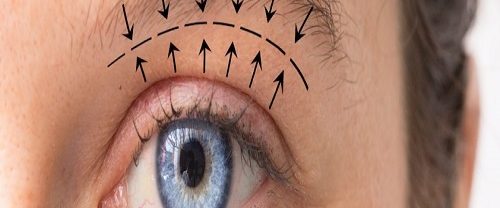

Kaş Kaldırma Nedir? Kaş kaldırma, genellikle yaşlanma süreciyle birlikte kaşların sarkması veya düşmesi sonucu ortaya çıkan estetik bir sorunu düzeltmek için yapılan cerrahi bir prosedürdür. Bu işlem, kaşların daha genç ve daha canlı bir görünüm kazanmasını sağlayarak yüzün genel estetiğini iyileştirir. İşte kaş kaldırma işlemiyle ilgili detaylar: Amacı: Kaş kaldırma işlemi, kaşların doğal yerine kaldırılarak…

Göz Kapağı Estetiği Blefaroplasti Nedir? Göz Kapağı Estetiği Blefaroplasti, göz kapağı estetiği olarak da bilinen bir cerrahi prosedürdür. Bu prosedür, yaşlanma belirtilerini azaltmak veya düzeltmek, göz kapaklarının sarkması veya torbalanması gibi kozmetik sorunları gidermek amacıyla yapılır. Genellikle üst ve alt göz kapakları için uygulanabilir. Üst göz kapağı blefaroplastisi, göz kapağının üst kısmındaki deriyi, kasları ve…

Göz Altı Torbası Ameliyatı Nedir? Göz altı torbası ameliyatı, genellikle estetik bir endişe kaynağı olan göz altında oluşan fazla yağ, deri ve doku birikimini azaltmak veya gidermek için yapılan cerrahi bir prosedürdür. Bu işlem, genellikle yaşlanma, genetik faktörler, stres, yorgunluk veya diğer çevresel etkenlerden kaynaklanan göz altı torbalarının neden olduğu belirgin şişlik ve torbalanma hissini…

Badem Göz Estetiği Nedir? Badem göz estetiği, genellikle göz kapağında görülen düzensizlikleri, sarkmaları veya torbalanmayı düzeltmek amacıyla yapılan bir kozmetik cerrahi prosedürdür. Bu estetik işlem, göz çevresindeki dokuların yeniden şekillendirilmesi ve germe işlemiyle gerçekleştirilir. Göz çevresindeki cilt yaşlanma, genetik faktörler, güneşin zararlı etkileri ve yaşam tarzı gibi çeşitli nedenlerden dolayı sarkabilir, torbalanabilir veya kırışabilir. Bu…